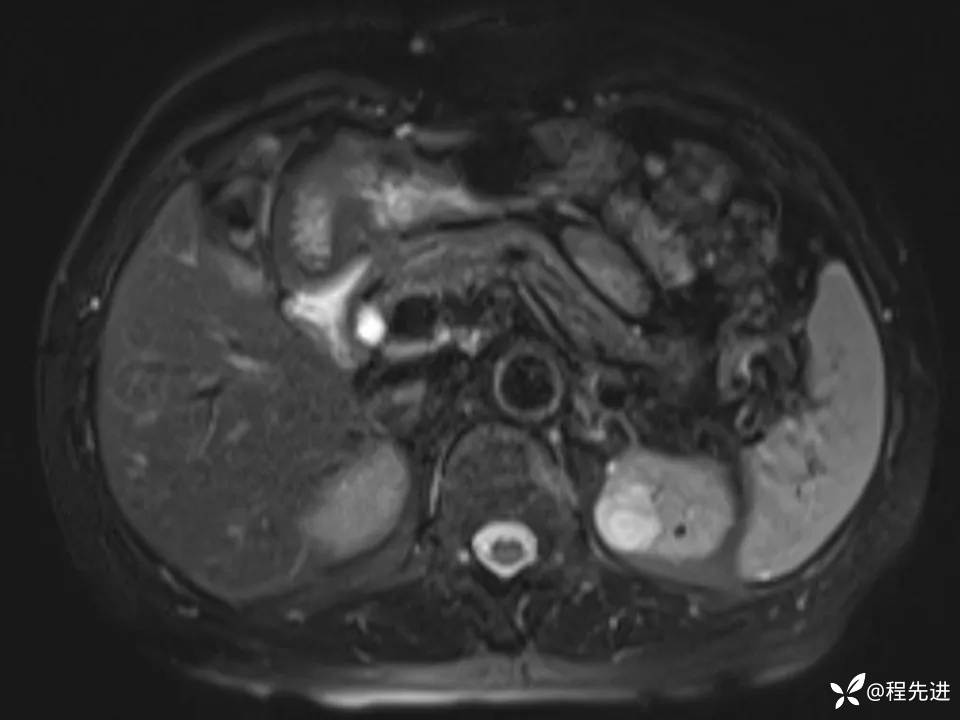

患者性别:女

患者年龄:67岁

简要病史:体检发现左肾占位,无临床症状,实验室检查无殊。

CT、MRI平扫+增强: